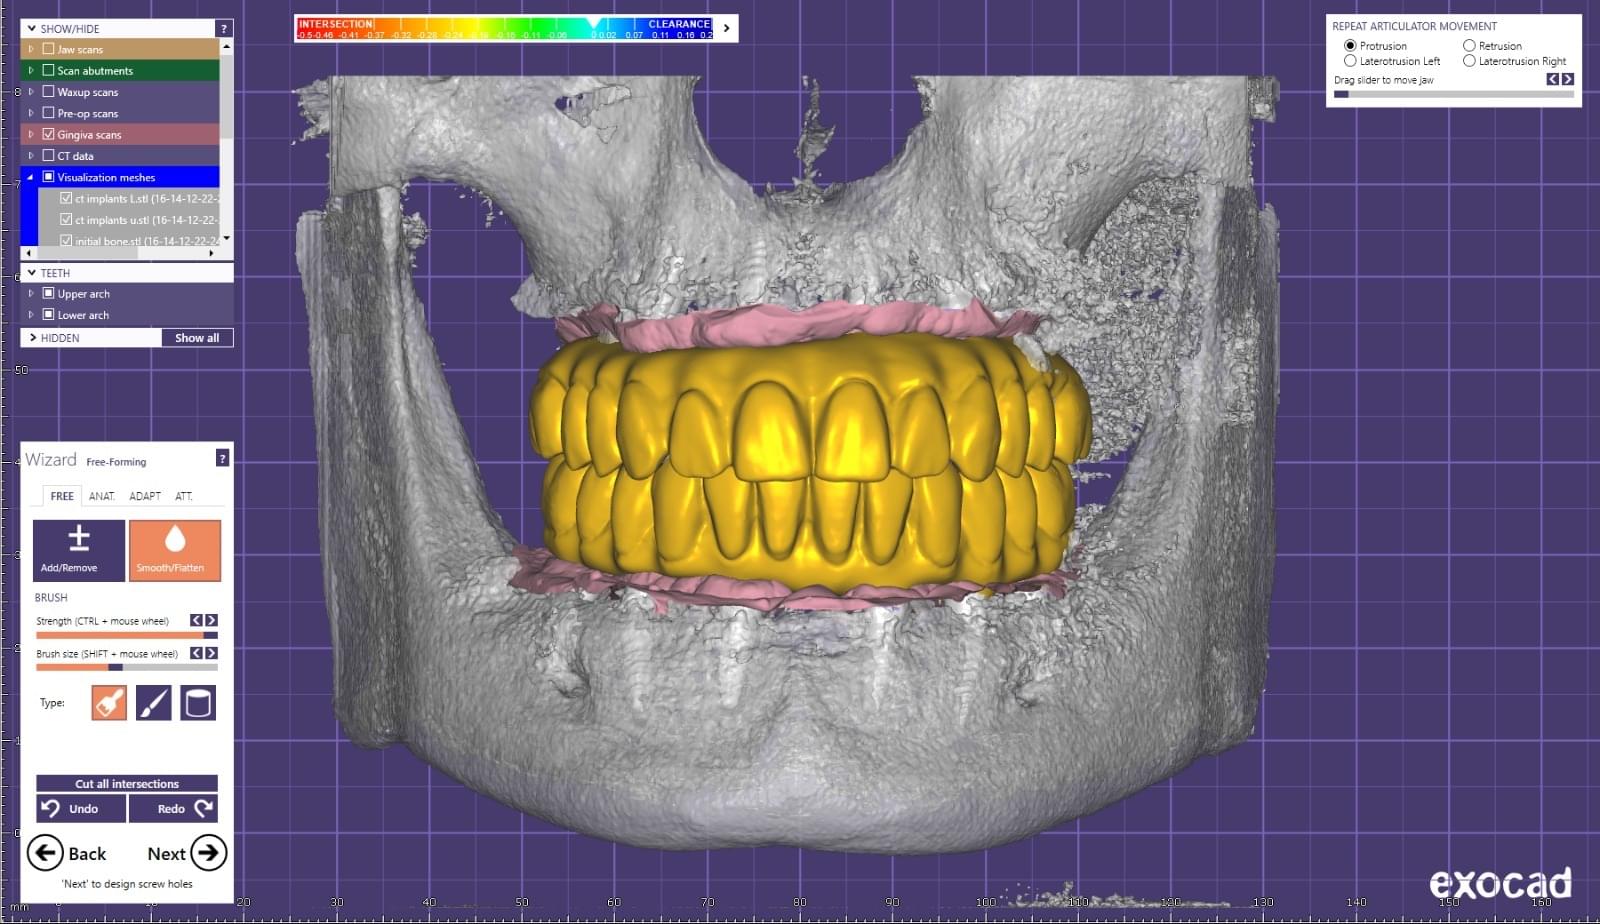

Progettiamo i denti al computer

Tecniche di design industriale applicate al dentale. Questo ci permette di ottenere risultati predicibili. I denti che montiamo in bocca ai nostri pazienti sono presi da librerie di forme di denti REALI digitalizzate. La progettazione viene in parte delocalizzata. Più Team da diverse parti del mondo lavorano ai tuoi denti. Infine montiamo i denti finiti in bocca, e resta una copia digitale salvata in Cloud per l'assistenza negli anni e per la ristampa di pezzi identici all'originale, in caso di problemi.

Sezione dedicata alla progettazione digitale dei nuovi denti.

In questo reparto vengono eseguite le rilevazioni da cui parte la progettazione dei denti provvisori e definitivi che gli Odontoiatri Protesisti monteranno sopra agli impianti.

Al suo interno vengono:

1. Scansionati Viso e Bocca

2. Fatte impronte digitali degli impianti posizionati dalla equipe chirurgica

3. Progettati i Mock-Up, le prove rapide per simulare il risultato che poi otterremo con i denti provvisori o definitivi.

4. Pianificare le forme dei denti masticatori in accordo con i movimenti mandibolari del paziente